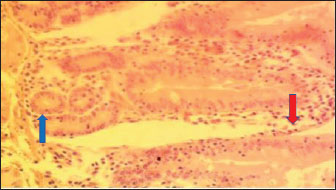

Fig. 4. (SNLM): Section of the intestine showing moderated necrosis of Crept of Lieberkühn (blue arrow) and mucosal (arrow head) epithelial cells, with infiltration of inflammatory cells (red arrow) (x400; H & E).

In the NLM shown in Figure 1, the mucosal lining was complete, with the Lieberkühn villi and crypts properly arranged. The epithelial layer, largely composed of absorptive enterocytes and goblet cells, was well preserved and did not show cellular erosion or necrosis (An et al., 2022). The lamina propria appeared to be free of inflammatory infiltrations, and the make-up was not atrophied or distorted, indicating a healthy mucosal barrier and optimum operational capacity (France and Turner, 2017). The TDLM (Fig. 2) had effects that showed cellular disintegration of the Lieberkühn crypts, signifying epithelial rejuvenation (Liu et al., 2019). At the same time, mucosal epithelial inner layer necrosis, shown by disturbed cellular structure and cytoplasmic degradation, suggests a distorted mucosal barrier that may amplify absorptivity, poor nutrient assimilation, and increased susceptibility to enteric pathogens (Chistiakov et al., 2014; De Medina et al., 2014). These observed changes can be due to the secondary metabolites like saponins, alkaloids, phenolics, and tannins present in Tithonia diversifolia, which are known to cause cytotoxic, anti-proliferative, and membrane-disrupting activities in the GIT tract when taken unprocessed (Abdelsalam and Fathi, 2023). These observations demonstrate the need for detoxification, quantification, and probably fermentation when incorporating TDLM into the diet of local rabbits (Abd-Elghany et al., 2021). Although TDLM provides a good source of nutritious and phytogenic benefits, its raw inclusion must be controlled to avoid compromising gut integrity and performance (Sugiharto et al, no date). In the observed PBLM in Figure 3, the necrosis in the crypt of Lieberkühn shows disturbance of the proliferative region crucial for epithelial regeneration and intestinal homeostasis (Chistiakov et al., 2014). Impairment of the crypts affects enterocyte production, which may cause weakened absorptive and digestive effectiveness in the small intestine (Buckley and Turner, 2018). Concurrently, mucosal epithelial cell degeneration and necrosis show intestinal barrier failure, increasing the danger of luminal antigen translocation and mucosal susceptibility (An et al., 2022). The permeation of inflammatory cells, mainly lymphocytes and macrophages, demonstrates a limited immune response that may be a reaction to epithelial injury caused by phytochemicals in Parkia biglobosa leaves (Franz et al., 2019). These bioactive constituents possess antioxidant and antimicrobial properties and may cause cytotoxic effects at high levels of inclusion in unprocessed form. Tannins and saponins can tamper with membrane integrity, modify gut microflora, and trigger mucosal irritation (De Medina et al., 2014). These effects are consistent with the inflammatory and degenerative changes observed in the duodenal mucosa (Chistiakov et al., 2014; De Medina et al., 2014). The observed necrosis in the crypt that controls epithelial cell production and mucosal renewal in rabbits fed SNLM indicates weakened cellular turnover (Buckley and Turner, 2018). Moreover, the loss of mucosal epithelial cells’ integrity shows that the absorptive and protective barrier is compromised, which is crucial for nutrient uptake and host protection (Liu et al., 2022). The infiltration of inflammatory cells, principally comprising lymphocytes and plasma cells, into the lamina propria, as shown in Figure 4, demonstrates an ongoing immune response that may have been prompted by mucosal or antigenic disturbance from biologically active compounds in Synedrella nodiflora. If the concentration is not regulated, this can lead to a cytotoxic or pro-inflammatory effect on the mucosa of the GIT (Jha et al., 2019). Specifically, saponins are known to disrupt membranes and increase gut penetrability, possibly leading to reactionary inflammation and epithelial damage (Ohimain et al., 2020). Necrosis of the Lieberkühn crypt observed in the LMM (Fig. 5) and damage to the mucosal epithelial cells affect the intestinal epithelium, compromising absorptive and secretory activities crucial for gut health (Buckley and Turner, 2018). This pattern is consistent with that observed in other leaf meals; however, the infiltration of inflammatory cells appeared mild, suggesting a moderate but continuous controlled immune response, possibly to clear away cellular fragments and restore mucosal integrity (Chistiakov et al., 2014; De Medina et al., 2014). This trend aligns with subacute intestinal damage, where soreness is present but not distressing, enabling mucosal recovery if the injurious stimuli are removed (France and Turner, 2017; An et al., 2022).